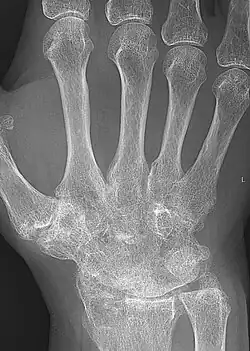

X-ray of the wrist of a woman with rheumatoid arthritis, showing unaffected carpal bones in the left image, and ankylosing fusion of the carpal bones 8 years later in the right image.